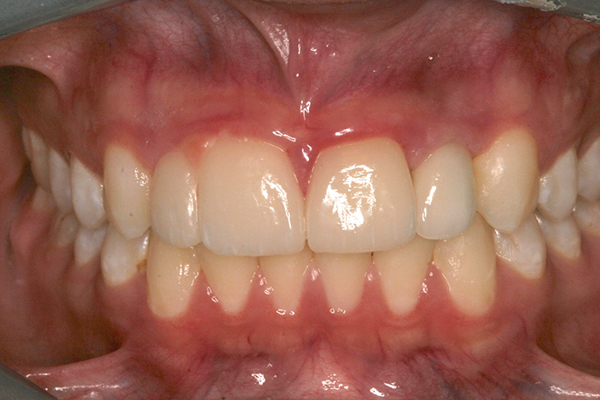

Fig 1 and Fig 2. Pretreatment photographs. Patient at 9 years of age on presentation.

A 9-year-old girl, referred to a prosthodontic office by her pediatric dentist, presented with her mother’s chief complaint: “The kids are teasing her about her big front tooth.” Findings from radiographic and clinical examinations revealed fused maxillary central-peg lateral incisors, teeth Nos. 7 and 8, and a congenitally missing lateral incisor, tooth No. 10 (Figure 1 through Figure 3). An implant was selected as the ideal treatment to replace tooth No. 10 when somatic growth was complete. A diagnostic wax-up was fabricated to determine if the fused tooth could be made to resemble two teeth, using pink composite to give the illusion of an interproximal papilla. The patient was referred for an orthodontic consultation to plan for closure of the diastema between teeth Nos. 8 and 9 and achievement of proper alignment for implant No. 10. The patient was also referred to a periodontist for pretreatment assessment of the tooth No. 10 site. An endodontist was consulted should exposure of the large pulp occur during tooth preparation.